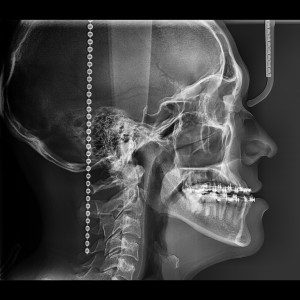

SERVICIOS 2D

SIALOGRAFIA